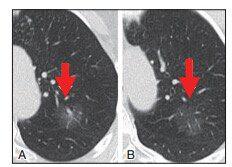

▲图3 A.CT平扫发现右上肺叶部分显示毛玻璃样密度结节,直径测量约17.64 mm,初步诊断为细支气管肺泡癌(BAC)可能,建议3个月随访观察。B.3个月后CT扫描图像显示GGN消失,证实为局灶性非特异性炎症